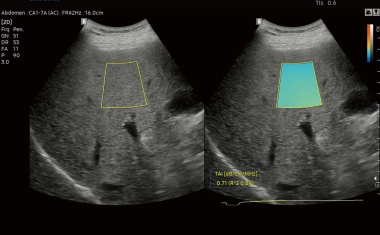

Mit dem neuen RS85 Prestige Ultraschallsystem integriert Samsung drei neue Messverfahren zur Quantifizierung von Lebersteatose.